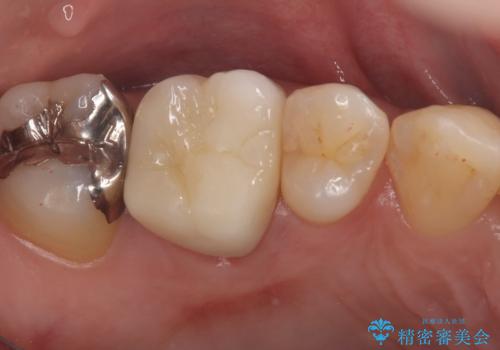

メタルクラウンを除去したところ近心面に大きな窪みとう蝕を認め、ファイバ-コアからのやり替えとしました。クラウンは審美性の良いセラミッククラウンを選択されました。

・オールセラミッククラウン(スタンダード):110,000円(税抜き)

・ファイバ-コア:20,000円(税抜き)